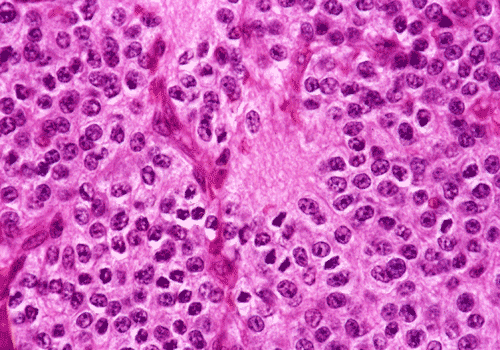

Panel A and B are low-magnification photomicrographs featuring solid sheets of isomorphous, small round to ovoid neoplastic cells with a delicate but rich vascular network. There are also intervening irregular patches of fibrillary neuropils. At high-magnification, the tumor cells appear as fairly uniform round to polygonal cells with perinuclear halo (Panel C). An island of neuropil is present in Panel D. The tumor cells are immunoreactive for synaptophysin (Panel E). The tumor cells were not immunoreactive for neurofilament proteins. At the ultrastructural level, the neoplastic cells contain numerous cell processes filled with vessicles and dense core granules (Panel F and G). Dense core granules and vescicles in high-mangification are shown in Panel H. The vesicles have structures similar to that of the synaptic vesicles, a feature of neuronal differentiation.

Histological, the tumor is composed of solid sheets of small, round to polygonal, isomorphic tumor cells with distinct cell membrane. Within the neoplastic cells is a delicate vascular network. Microcalcifications, when present, are distributed throughout the tumor. The cytoplasm is fine and amphophilic. Perinuclear halo is usually present and prominent, leading to an impression of a clear cell tumor. The summation of these features generates a “honey-comb” pattern similar to that of oligodendroglioma and clear cell ependymoma. The nuclei of neurocytoma are round, small, and contain fine and speckled chromatin. Nucleoli are indistinct. Mitotic figures are not readily seen or infrequent. Irregular and small islands of neuropils are present. Perivascular arrangement of neuropils in some areas may closely mimic the coronary perivascular fibrillary hypocellular mantles (perivascular pseudorosettes) that are considered evidence of ependymoma. The real ependymal pseudorosettes are more orderly and fibrillary. A high index of suspicion is important to avoid this trap.